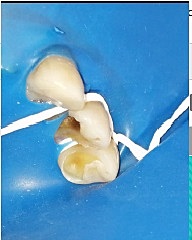

• Tercera cita reconstrucción del órgano dentario 2.5

Tercera cita reconstrucción del órgano dentario 2.5

Al paciente se le reconstruyó el órgano dentario 2.5 con resina compuesta por una fractura coronaria en la cúspide palatina.